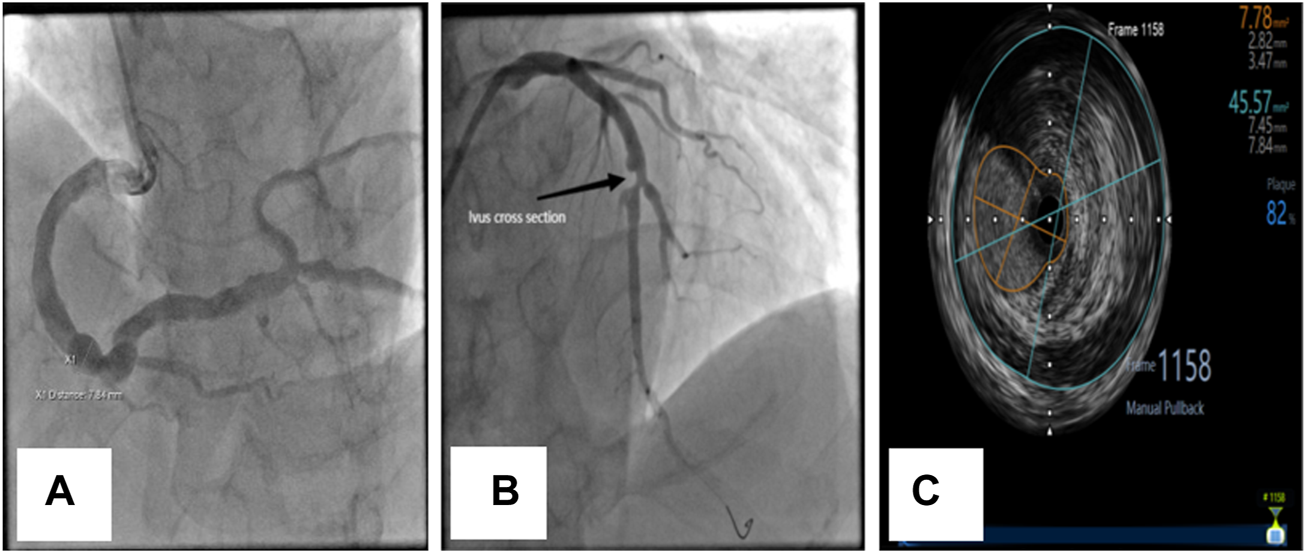

FIGURE 1

Coronary angiographic and intravascular ultrasonographic (ivus) images of CAE. (A) Diffuse dilation of the right coronary artery. (B) Diffuse dilation with significant atherosclerosis and stenosis of the left anterior descending (LAD) coronary artery in the same patient. (C) Ivus image of LAD.